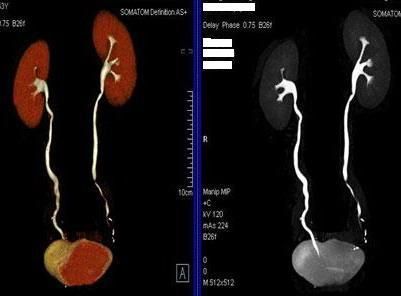

4、腎動脈血管成像(腎動脈狹窄):

5、下肢動脈血管成像:

四、全尿路成像及骨關節三維成像。

全尿路成像(CTU):